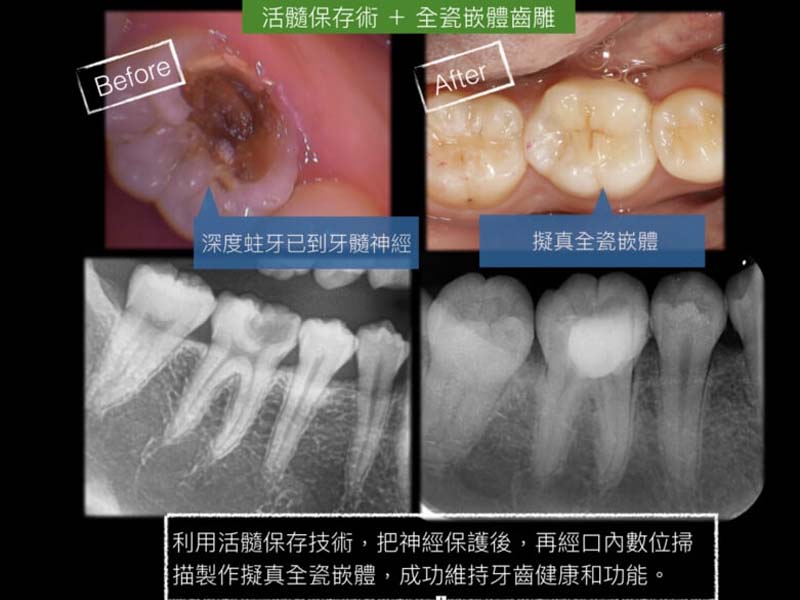

活髓保存+微創全瓷美學修復